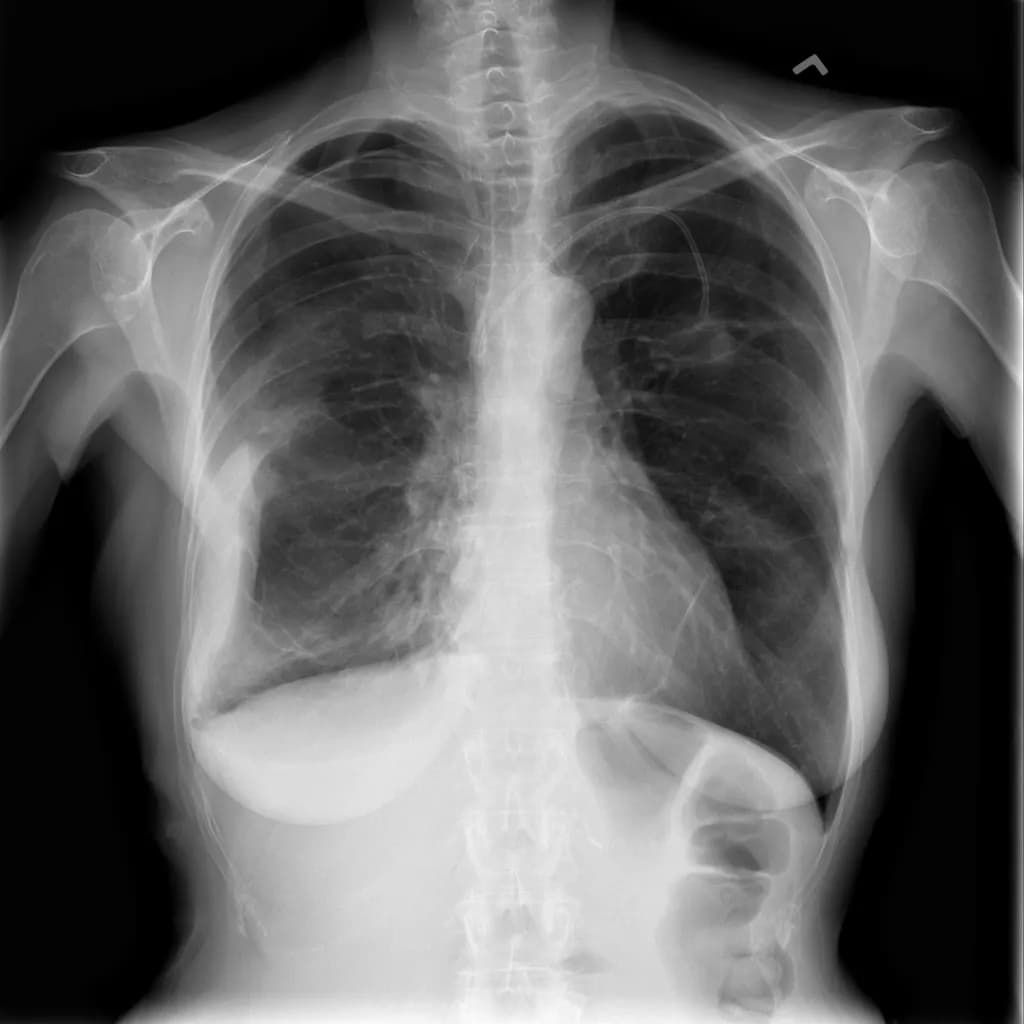

Musculoskeletal X-ray AI Analysis

부위를 클릭하여 결과 이미지를 확인하실 수 있습니다.